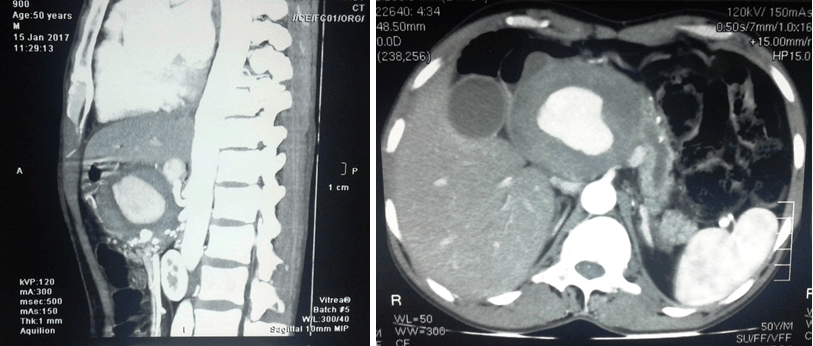

Contrast enhanced computed tomography scan of the abdomen showed a pseudoaneurysm in the superior pancreaticoduodenal artery. Superiorly there was a linear high density within the hypodense wall which could be contrast leak into intramural thrombus. Pancreatic head is compressed and there are multiple foci of coarse calcifications within the head of the pancreas. Pancreatic duct is dilated (9.1 mm). Second part of the duodenum is compressed by the lesion. Gallbladder is distended and common bile duct is dilated (1.3 cm). Hepatic artery originates directly from the aorta.

Figure 1: Contrast-enhanced computed tomography scan of the abdomen showing a pseudoaneurysm in the superior pancreatico duodenal artery.